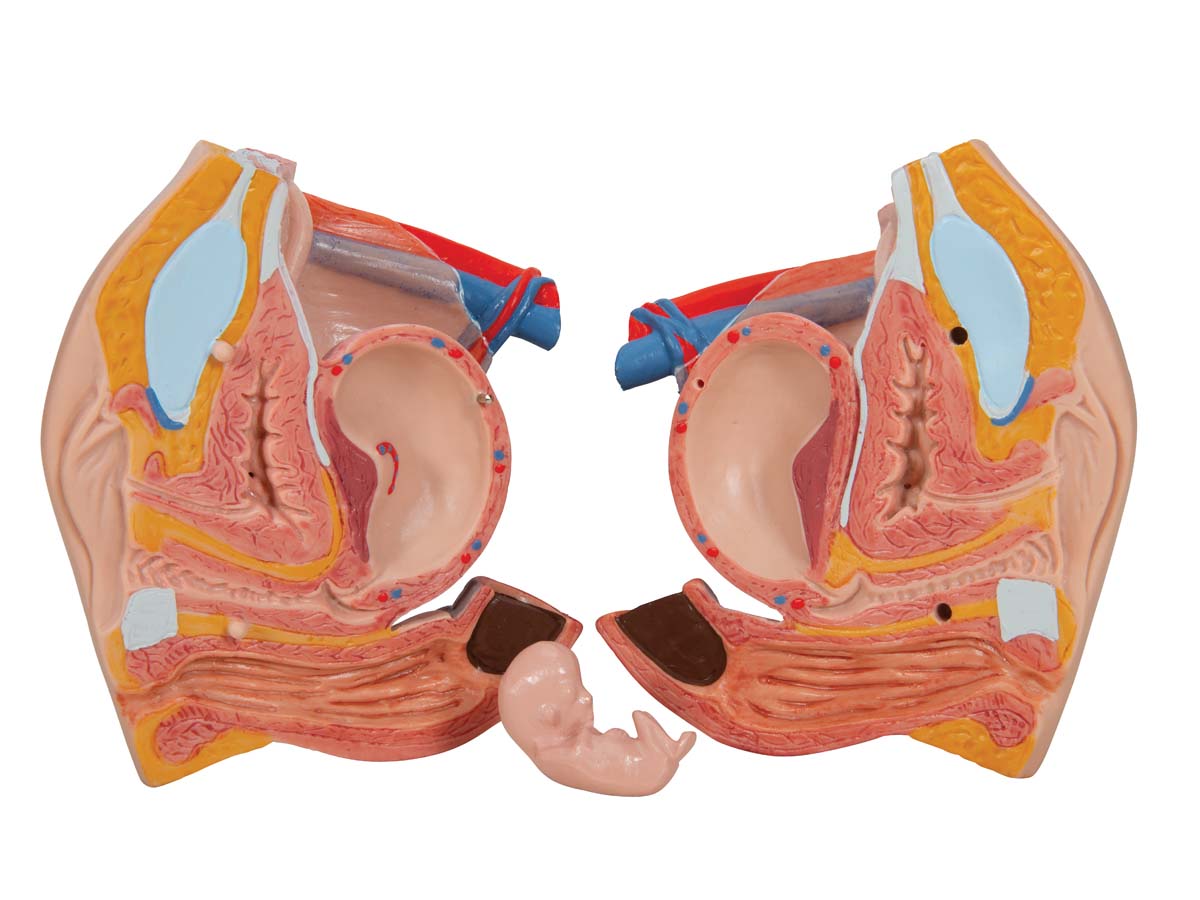

Luxus Torso Modell, mit weiblichen & männlichen Geschlechtsorganen, 24-teilig

Luxus Torso Modell, mit weiblichen & männlichen Geschlechtsorganen, 24-teilig – 3B Smart Anatomy

Der 3B Scientific Luxus-Torso bietet Ihnen alle Möglichkeiten für ausführliche Demonstrationen. Sie erhalten hunterprozentige Qualität und einen hohen Grad an Detailarbeit. Die Beschaffenheit der erweiterten Torso-Version ist beeindruckend, genau wie sein Preis! Beantworten Sie mit seiner Hilfe alle Fragen zur inneren Anatomie des Menschen. Er ist zerlegbar in:

– 3-teiliger weiblicher Genitaleinsatz mit Embryo

Alle Organe in diesem menschlichen Torso sind von Hand bemalt.

7. Möglichkeit zum Erlernen der männlichen und weiblichen Anatomie